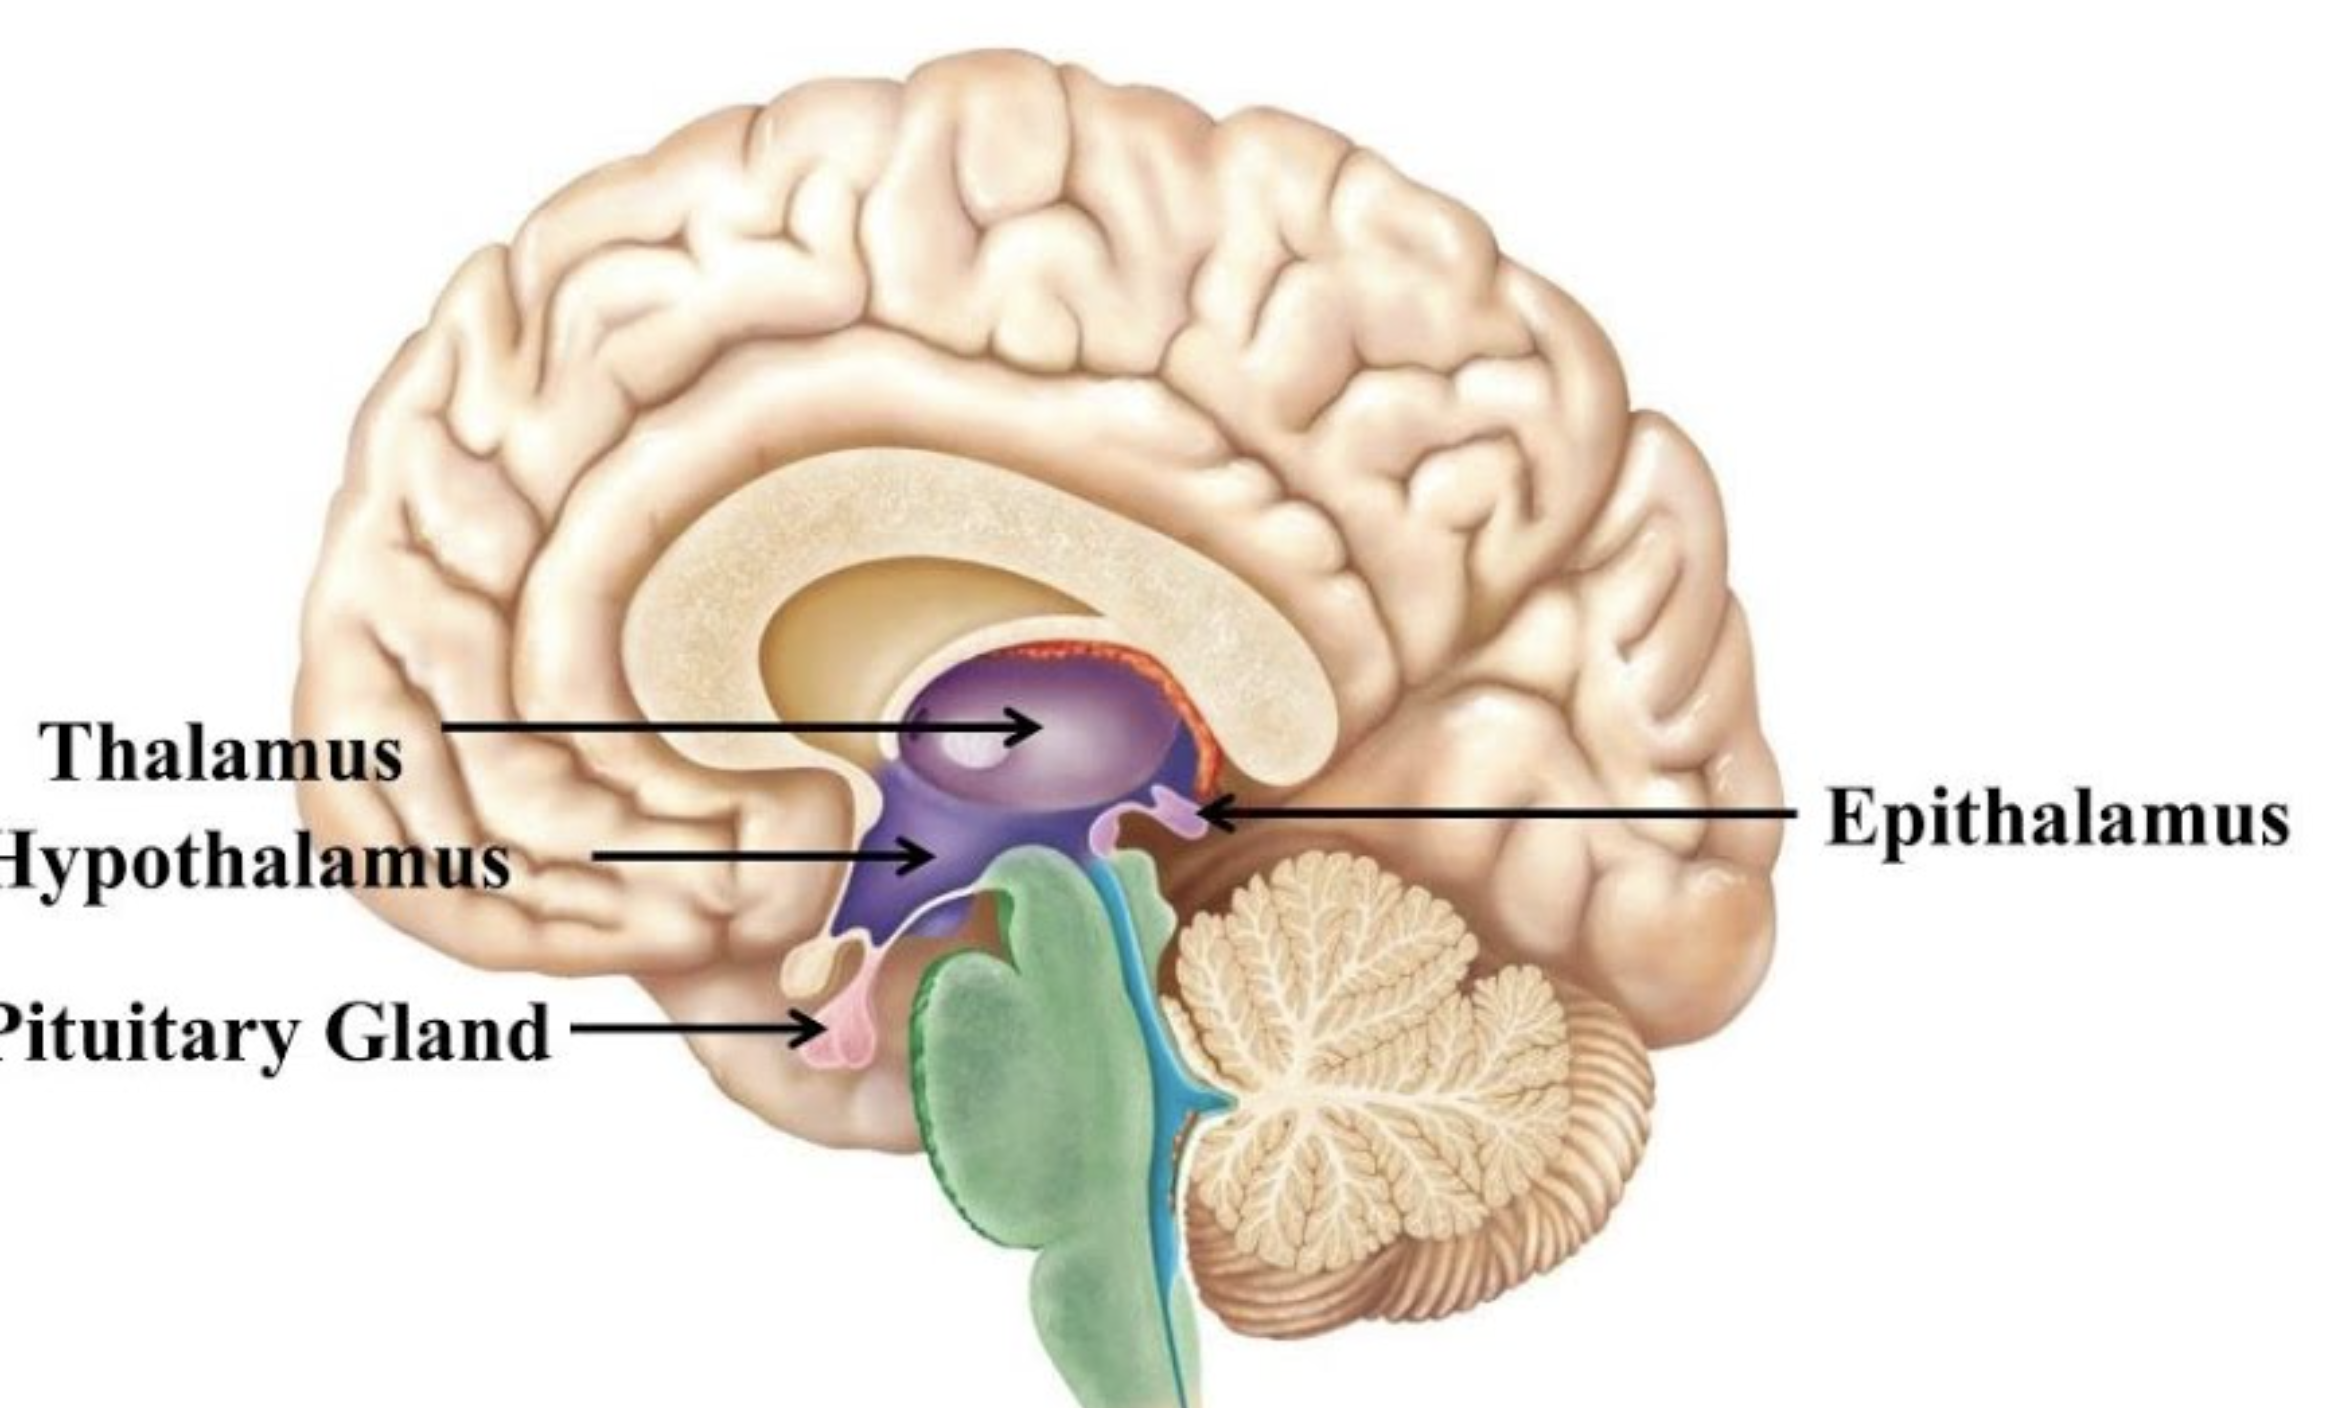

Which Diencephalon structure contains the Pineal Gland(secretes Melatonin)

Epithalamus

Which structure is a switchboard where neurons synapse to get to the precentral gyrus?

Thalamus

Which structure is the master control of the ANS and endocrine system, and regulates body temp/sleep/intake?

Hypothalamus